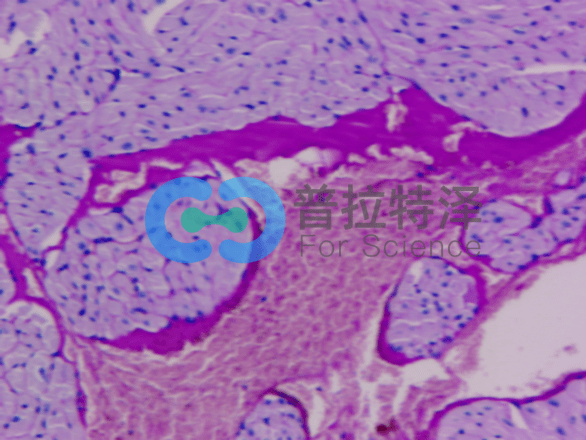

③消化道疾病診斷

在消化道疾病的診斷中,PAS染色對于觀察腸黏膜結構、黏液分泌及炎癥浸潤等具有重要意義。通過PAS染色,醫生可以判斷腸道疾病的類型及病變程度,為治療方案的制定提供依據。